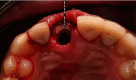

Anterior aesthetic zone implant placement and tooth restoration can be a quite challenging procedure. Modern technology offers new tools that can help maximize results in both aesthetic and functional ways. The socket-shield technique, as described by Hürzeler et al., boosted with the 3D diagnostics, digital planning, and 3D printing, could provide a valuable alternative to traditional approaches. This case report describes a clinical workflow for an efficient anterior implant-prosthetic restoration.